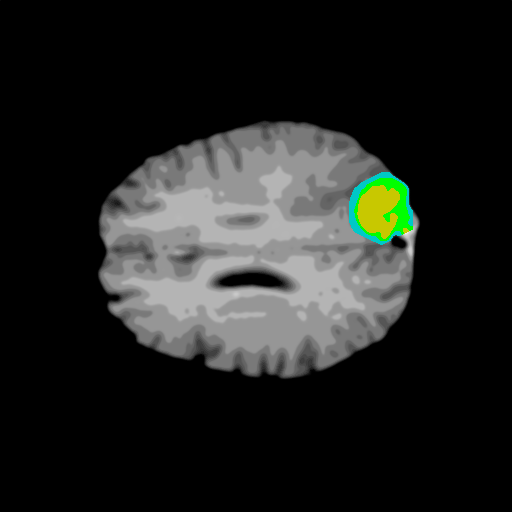

Extensive experiments have been performed in the current setup, and experimental outcomes are reported with the demonstration of numerical and statistical analyses using the proposed QFS-Net, QIS-Net [39], convolutional U-Net [18] and Residual U-Net (URes-Net) architectures [20]. The human expert segmented skull-tripped contrast enhanced DSC brain MR input image slices of size and ROIs are provided in Figure 5 as samples. The demonstration of QFS-Net segmented images followed by the essential post-processed outcome on the slice no. for class level with four distinct activation schemes () are shown in Figure 6. It is evident from the experimental data provided in Table LABEL:tab1 that the proposed QFS-Net performs optimally for the -connected quantum fuzzy pixel information heterogeneity assisted activation () with and gray scale set in comparison with other thresholding schemes and gray scale sets under the four evaluation parameters () [44]. The segmented tumors obtained using the proposed self-supervised procedure under class transition levels with four different thresholding schemes , , and are demonstrated in Figures 7- 8 for the class boundary sets and [39], respectively. The segmented images using the remaining two class boundary sets ( and ) [39] are provided in the supplementary materials section. The segmented ROIs describing the whole tumor region after the masking procedure using QIS-Net, U-Net and URes-Net are also reported in Figure 9.